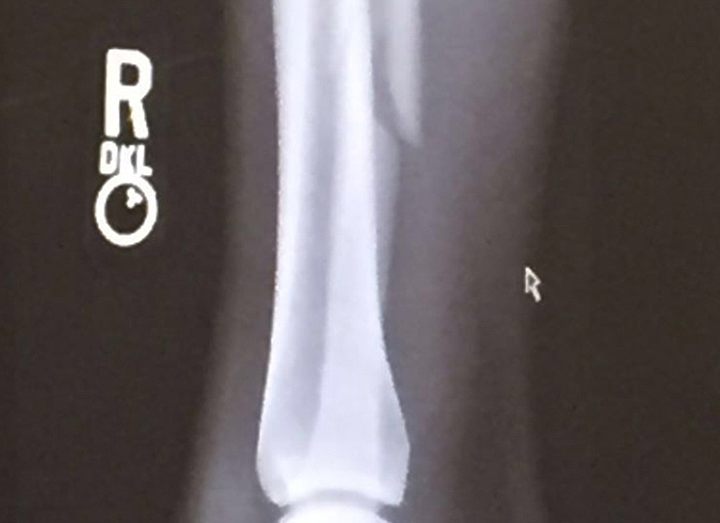

Питбуль сломал малоберцовую кость голени

Экс-чемпион Bellator в полулегком весе, Патрисио «Питбуль» Фрейре, во втором раунде отказавшийся продолжать поединок с Беном Хендерсоном, получил перелом малоберцовой кости голени.

«Я сломал голень еще в первом раунде, когда мой удар ногой был сблокирован коленом», - сообщил бразилец в Инстаграм. «Я был в состоянии передвигаться еще половину второго раунда, но чувствовал, как движется сломанная кость. Я действовал уверенно и собирался выиграть этот бой. Я скоро вернусь»